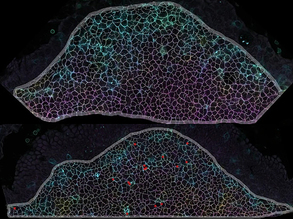

Brain Genes Identified